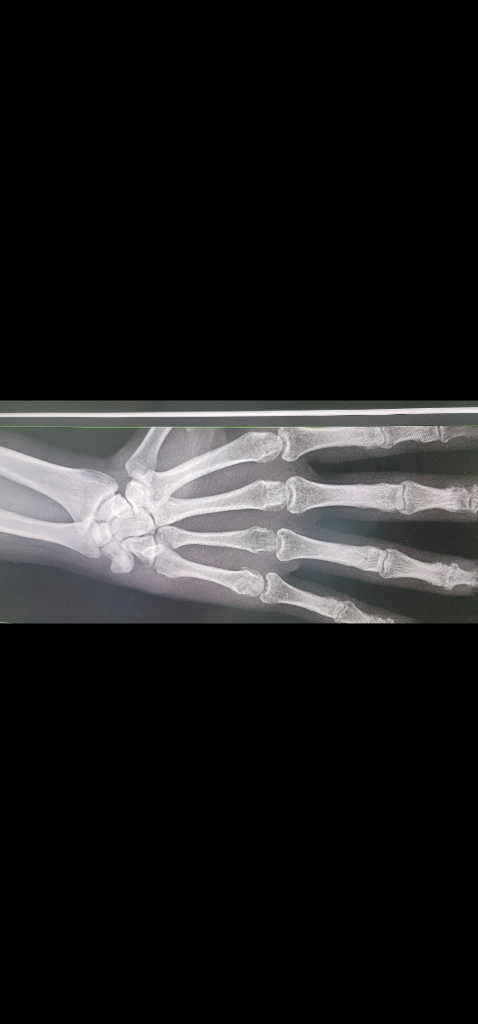

오른손 네번째 손가락 중수골 골절로 핀 고정술로 치료받고 8주차 입니다. 핀은 2주 전에 제거하고 재활하고 있습니다. 수술한 병원이 거리가 있어서 근처 병원에서 엑스레이 촬영 후 진료 봤습니다.

1. 네번째 중수골 수술한 부위 뼈가 붙었는가?

2. 손목뼈(네번째, 다섯번째 중수골 끝 부분)에 긴 타원형으로 보이는 흰색점은 이상 없는가?

입니다. 의사 분이 그 부위를 만져봤을 때 통증이나 특이점은 없었습니다.

• 1번 째 사진